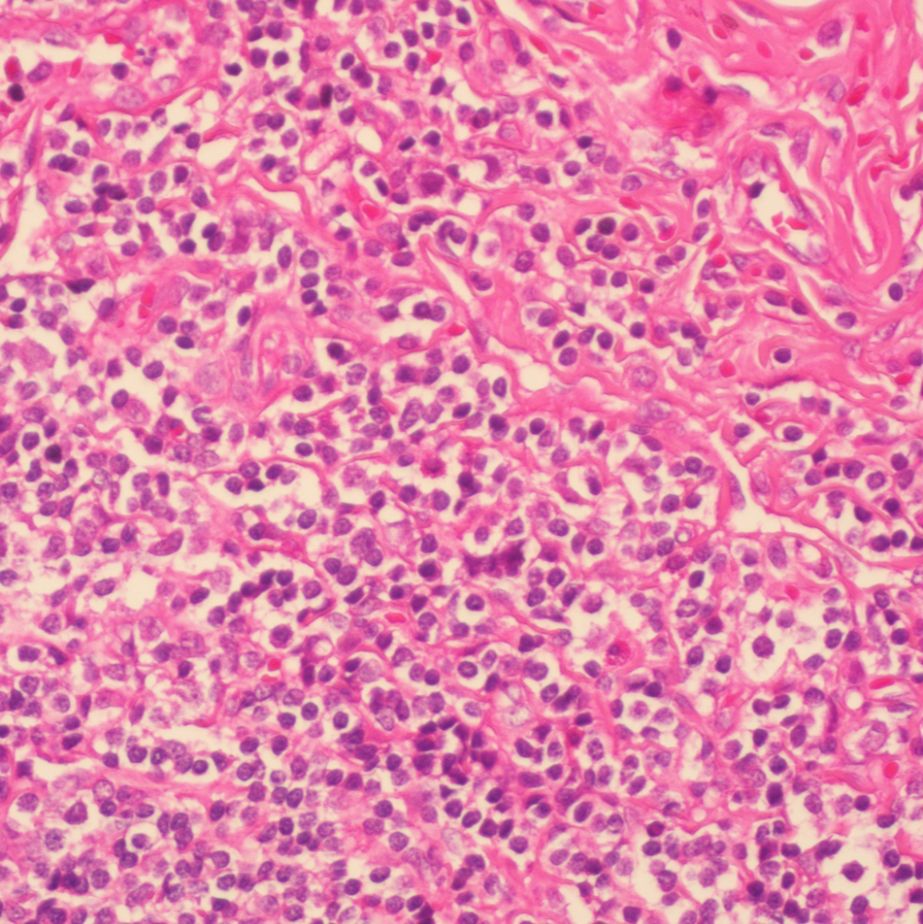

预期用途: 用于各种细胞、组织石蜡切片、冰冻切片、火棉胶切片、树脂切片、涂片、印片的染色

;DAB 显色时间很短(如几秒或几十秒)就出现很深的棕褐色,这很可能说明你的抗体浓度过高或抗体孵育时间过长,需要下调抗体浓度或缩短你的抗体孵育时间;此外,若很短时间就出现背景很深,还有可能你前面的封闭非特异性蛋白不全,需要延长封闭时间;DAB 显色时间很长(如超过十几分钟)才出现阳性染色,一方面可能说明你的抗体浓度过低或孵育时间过短(最好一抗 4 ℃过夜);另一方面就是封闭时间过长。 12)复染 目的是形成细胞轮廓,从而更好地对目标蛋白进行定位,经常用苏木素复染(胞

隆抗体]、生物素化山羊抗小鼠IgG、试剂SABC,最后DAB显色,苏木素复染,酒精梯度脱水,二甲苯透明,中性树胶封片,显微镜下观察。2 结果 2.1 体外培养的胎儿脐动脉血管平滑肌细胞的形态观察 实验中观察到脐动脉组织块贴壁后5~7d可见有细胞以垂直方向从组织块周围游走出来(见图1),但并不是所有的组织块周围都有细胞游出,离组织块较远的区域也可以看到细胞,此为平滑肌细胞的漂移性生长特性(见图2),细胞形态多样,大小不一,多为长梭形、菱形或星形; 9~11 d细胞进入对数生长期,细胞生长加速,部分